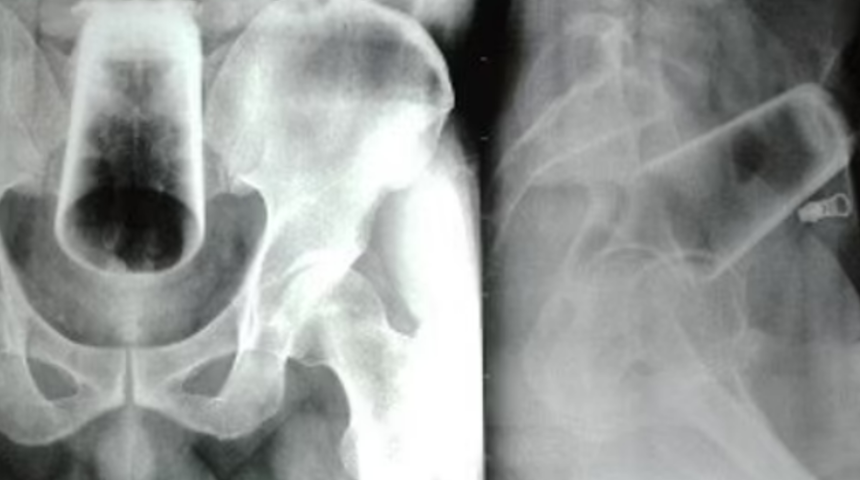

Röntgen taramaları, üst rektum ve kolonda ters çevrilmiş bir su bardağı gösterdi. Doktorlar, bardağın 'çıkarıldığında' kırılacağı korkusuyla, sağlık görevlilerinin üzerinde ışık bulunan esnek bir tüp kullanarak sigmoid kolonun içine bakmasına izin veren bir prosedür olan sigmoidoskopi yapmayı reddetti. Ancak hastanede adamın rektumundan camı çıkarmaya yönelik ilk girişimler başarısız oldu.